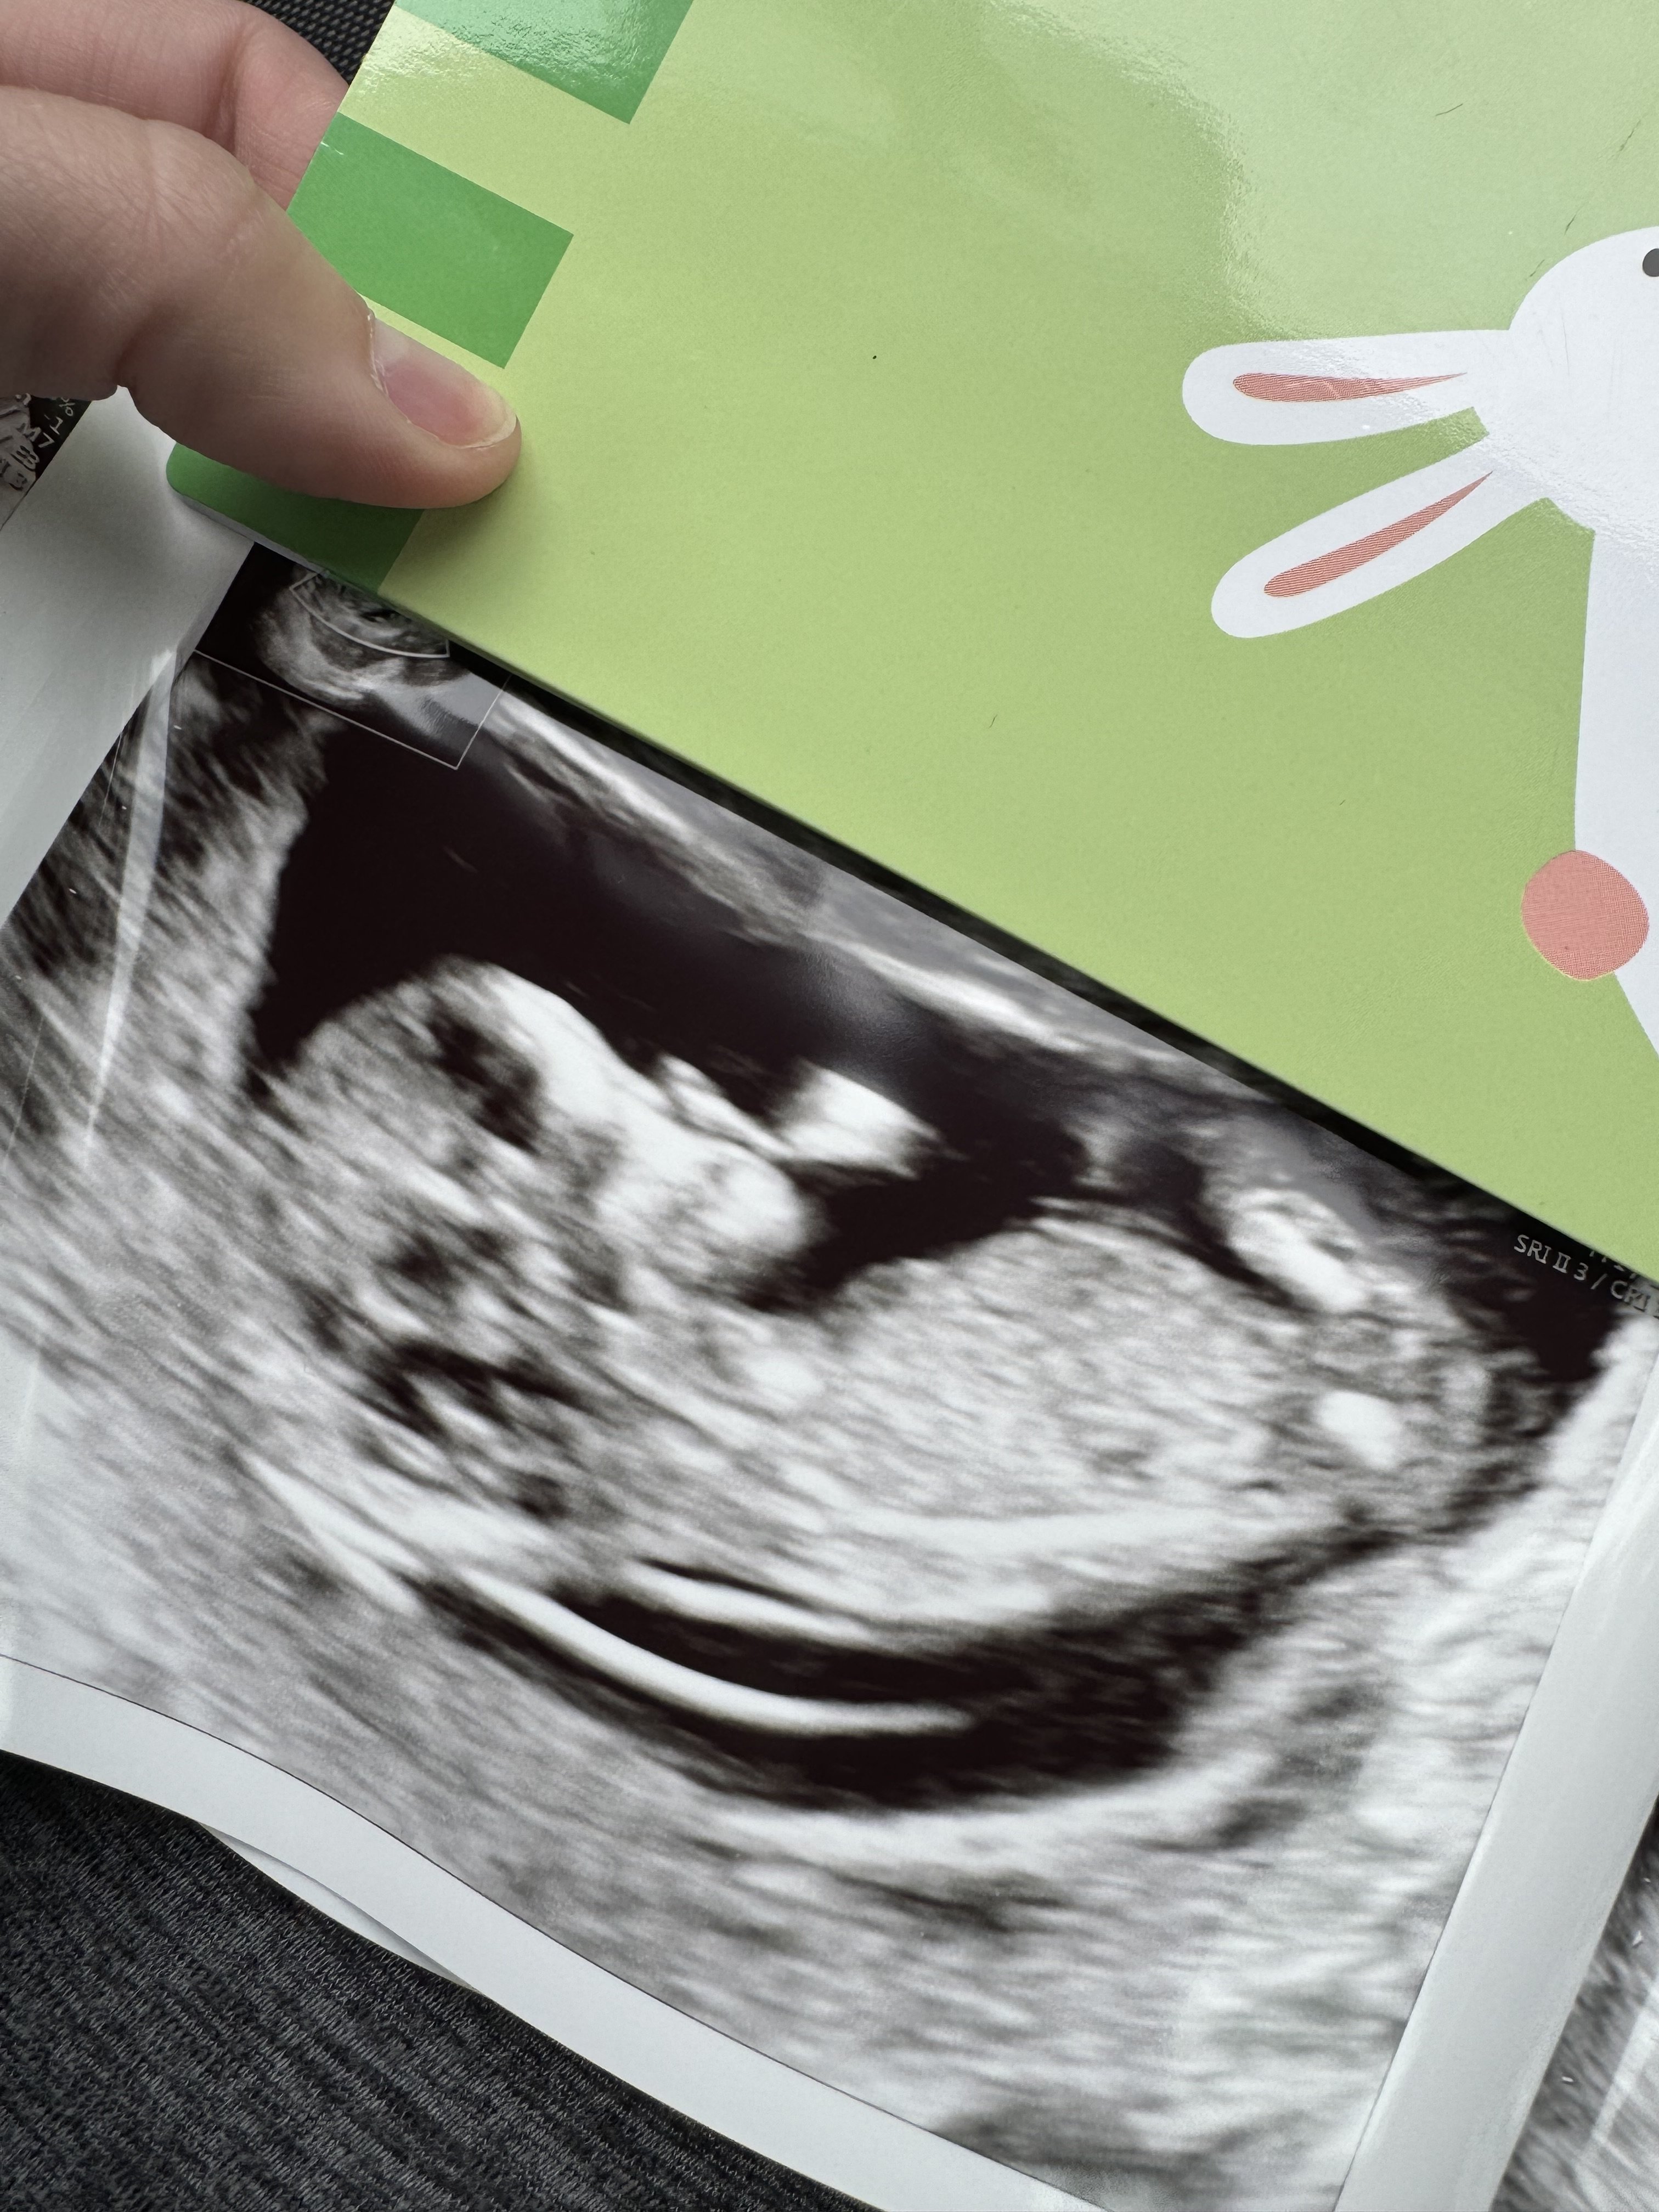

Näkyisköhän tässä?Ei näy mun silmään.![]()

Näkyy!!!!!!! Tosi tyttömäinen, mutta vielä on pieni mahdollisuus nousta pojaksi. Jos haluat tai sulla on face niin kannattaa kysyä nubtheoryqueens ryhmästä. Siellä on kätilöitä arvioimassa ja osuvat tosi usein oikeaan. Mä en aina huomaa semmoista pieniä merkkejä mitä ammattilaiset huomaa.Näkyisköhän tässä?![]()

Ok kiitos sulle! Yritin sinne jo laittaa mut eivät virlä hyväksyneet. Tyttö oiskin ihan kiva kun poika jo ennestään :)Näkyy!!!!!!! Tosi tyttömäinen, mutta vielä on pieni mahdollisuus nousta pojaksi. Jos haluat tai sulla on face niin kannattaa kysyä nubtheoryqueens ryhmästä. Siellä on kätilöitä arvioimassa ja osuvat tosi usein oikeaan. Mä en aina huomaa semmoista pieniä merkkejä mitä ammattilaiset huomaa.![]()